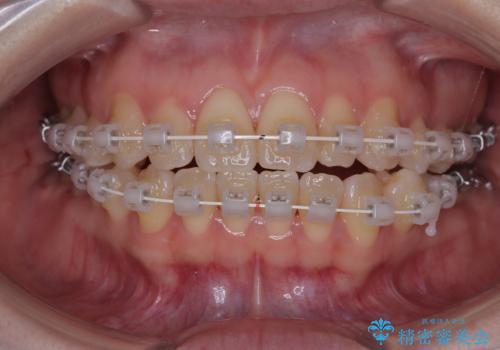

- 矯正装置

- 審美装置

という患者様のご希望を踏まえ、プラスチックブラケット+コーティングワイヤーを用いたワイヤー矯正を選択しました。

この方法は、

金属色が目立ちにくく審美性が高い

確実に歯を動かせるため治療計画が立てやすい

といったメリットがあります。